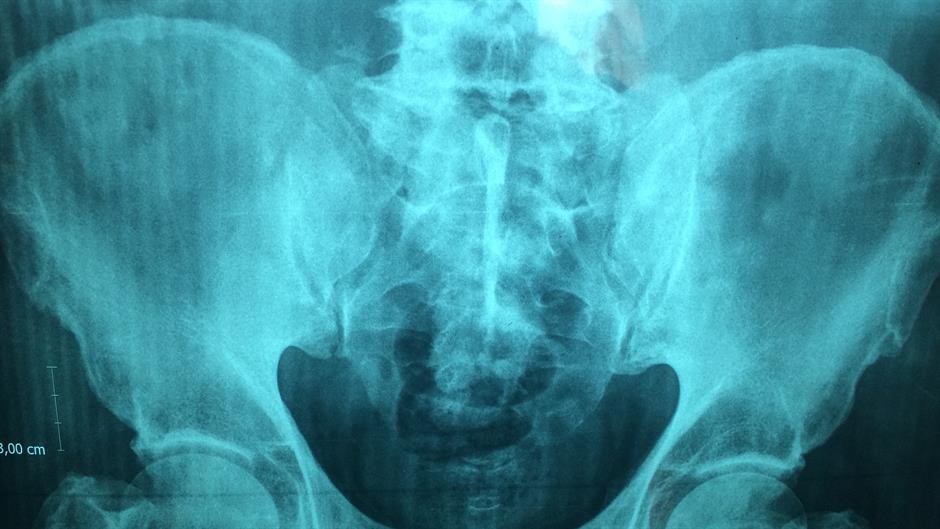

Naučnici su uspjeli klasifikovati jedan sasvim novi organ u ljudskom tijelu i to jedan koji se dugo skrivao u našem probavnom sistemu, a bio je praktički pred očima naučnika svo vrijeme.

Iako je struktura ovog organa poznata, njegova funkcija još uvijek je misterij za naučnike pa bi njegovo proučavanje moglo biti ključno za liječenje abdomenalnih i probavnih bolesti.

Novi organ nazvan je Mezenterij, nalazi se u našem probavnom sistemu te se dugo mislilo kako se sastoji od fragmentiranih i odvojenih struktura. No, posljednja istraživanja pokazala su da se zapravo radi o jednom sasvim novom organu.